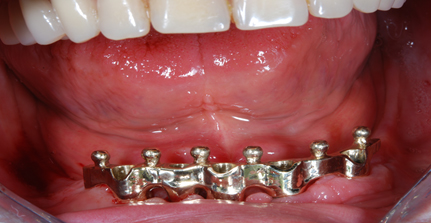

I denti irrecuperabili dell'arcata superiore ed inferiore del paziente di anni 65

sono stati sostituiti da 10 impianti, cioè protesi radicolari endo-ossee che sostengono le protesi fisse superiore ed inferiore.